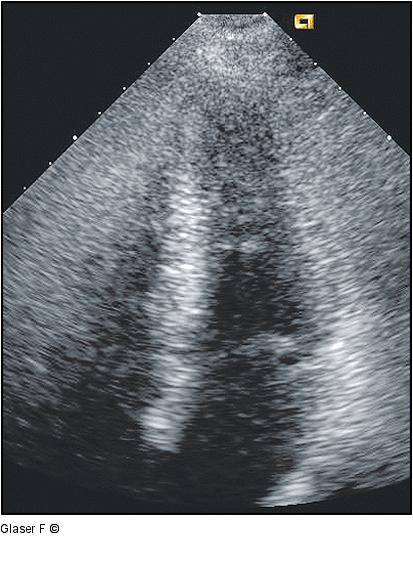

Abbildung 8: Hyperkinetische Herzaktion Nach Absetzen von Tenoretic hyperkinetische Herzaktion mit "Zusammenschlagen" von Septum und Lateralwand. |

Nach Absetzen von Tenoretic hyperkinetische Herzaktion mit "Zusammenschlagen" von Septum und Lateralwand. |